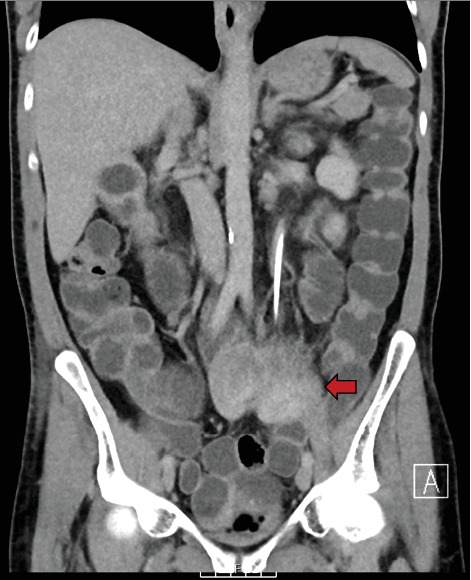

Background: Ureteric small bowel fistulas are rare entities, with limited reports in the literature. These pathological connections between the ureter and small bowel can lead to recurrent upper urinary tract infections and pose significant diagnostic and therapeutic challenges. The primary cause of ureteric small bowel fistula formation is iatrogenic intervention, such as percutaneous nephrolithotomy (PCNL) or abdominal surgery involving tissue resection. However, they can also arise spontaneously due to local chronic inflammation and infection. Given their rarity, there is no standardised management pathway, and the treatment approach should be individualised. Case Presentation: We present the case of a 57-year-old man presenting with a history of extensive locally advanced distal sigmoid carcinoma, managed with Hartmann's procedure with end colostomy followed by adjuvant radiotherapy and chemotherapy. He later developed a mid-ureteric small bowel fistula, presenting with urosepsis, a high-output stoma, deteriorating renal function and severe metabolic acidosis. Conservative management with regular ureteric stent exchanges every 3-4 months has successfully preserved renal function and improved his quality of life. Surgical closure was not pursued due to high operative risk, and repeat imaging has shown no evidence of persisting fistula, suggesting possible spontaneous closure. Conclusion: The treatment options for this ureteric small bowel fistula were limited. A lifelong nephrostomy was deemed unsuitable due to incompatibility with the patient's profession, and surgical intervention was associated with significant complexity due to the patient's history of malignancy and radiotherapy-related tissue changes. Therefore, a conservative strategy involving serial ureteric stent exchanges was pursued. Early recognition and individualised treatment of ureteric-enteric fistulas are essential, as timely intervention can significantly enhance prognosis and quality of life.

Abstract Image